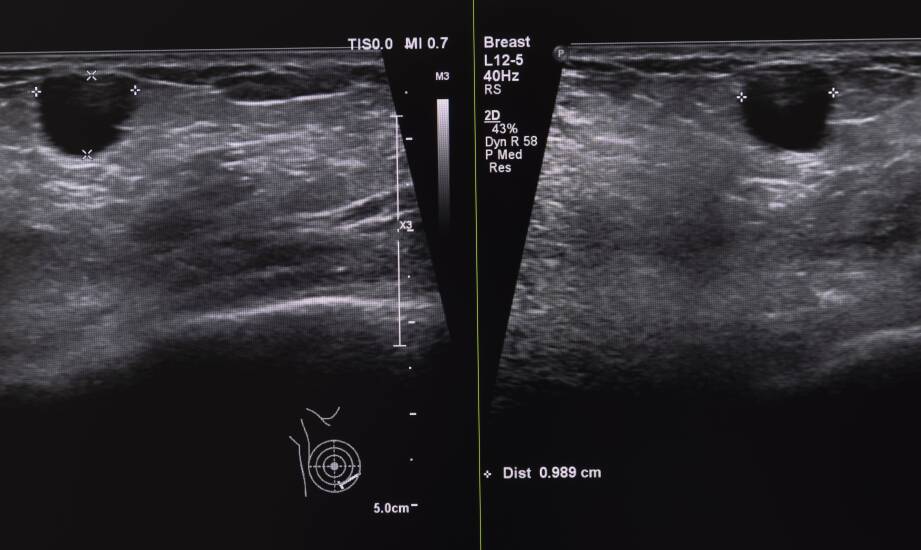

Wykrycie zmian w badaniu ultrasonograficznym piersi to moment, który dla wielu kobiet może wiązać się z niepokojem i licznymi pytaniami. USG jest jedną z podstawowych metod diagnostycznych, pozwalającą na szybkie i bezpieczne zidentyfikowanie nieprawidłowości w tkankach piersi. Zrozumienie wyników badania ma kluczowe znaczenie, ponieważ umożliwia lekarzowi dobranie odpowiednich dalszych kroków diagnostycznych lub terapeutycznych.

Po stwierdzeniu nieprawidłowości w USG piersi wdraża się zróżnicowane metody leczenia, dostosowane do rodzaju i charakteru zmian.

Terapie minimalnie inwazyjne – pozwalają na ograniczenie ingerencji w organizm i krótszy czas rekonwalescencji. Przykładem może być biopsja cienkoigłowa lub gruboigłowa, które umożliwiają dokładne zbadanie fragmentu tkanki.